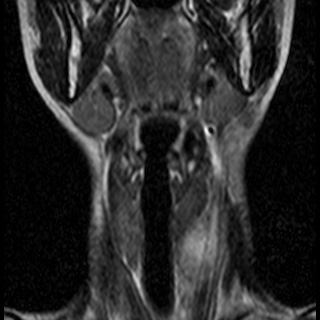

Невринома множественная шейного отдела с врастанием в спинно-мозговой канал

Здравствуйте! Мне 27 лет. Я стала жаловаться на головокружение, головные боли, пульсирование в голове. После исследования мрт выявилась следующая патология . Документы предоставляю. Можете ли Вы помочь в этой патологии? Как попасть к Вам на консультацию, учитывая эпидемиологическую обстановку? Спасибо.